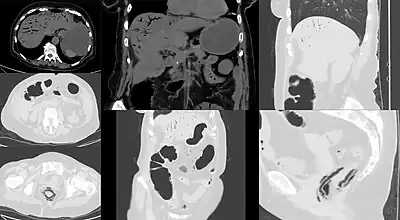

![]() | |

| Computed tomography (CT) showing dilated loops of small bowel with thickened walls (black arrow), findings characteristic of ischemic bowel due to thrombosis of the superior mesenteric vein. | |